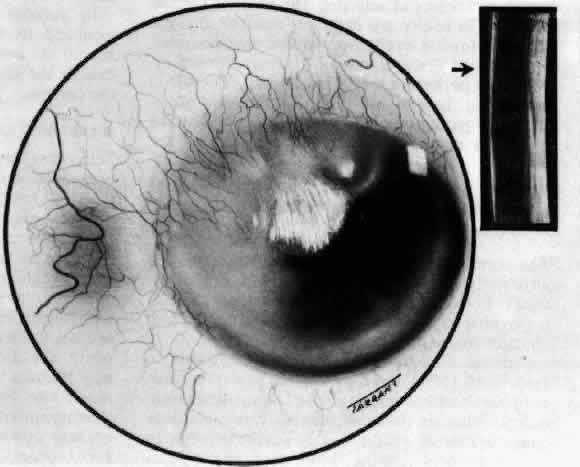

Necrotizing Anterior ScleritisdWithout Adjacent Inflammationd(Scleromalacia Perforans) Necrotizing anterior scleritis without adjacent inflammation appears to be a well-defined condition with little relation in clinical features to necrotizing scleral disease, even though the pathology is similar and the final result is the same. Scleromalacia perforans is characterized by the almost total lack of any symptoms. It occurs almost exclusively in patients with long-standing polyarticular rheumatoid arthritis, the majority of whom are female (Figs. 49 and 50; Color Plate 1E).

The anterior sclera loses its covering of episclera and develops an area of yellow-white necrotic slough over many months; this eventually separates or is absorbed, leaving the underlying choroid covered by either conjunctiva or nothing at all. As with necrotizing disease, the choroid does not bulge into this ectatic area; but unlike necrotizing disease, spontaneous healing of even small perforations is very limited once the necrotic tissue has been removed (see Fig. 50). Fluorescein angiography is not helpful, except to indicate areas of vascular closure in an otherwise extremely thin, atrophic episcleral tissue.4 The formation of a sequestrum appears to be caused by arteriolar closure as opposed to the venular disease seen in the other forms of necrotizing scleritis. Posterior Scleritis Because the posterior sclera is invisible, the diagnosis of posterior scleritis is made only if the anterior sclera is also involved or some other sign or symptom leads one to suspect it. Posterior scleritis is much more common than previously suspected, as recent clinical and pathologic studies have shown.19,28,29 There are two distinct forms of posterior scleritis. The first is usually associated with an anterior scleritis. This granulomatous disorder, like its anterior counterpart, can be diffuse, nodular, or necrotizing in character and is associated with the connective tissue diseases. The second form occurs in young patients of all races who are 9 to 40 years of age. It is always diffuse in character but is not associated with any systemic disorder. Both forms may cause uveitis if the inflammation affects the ciliary body, and in both forms the patient may develop exudative retinal detachments, choroidal folds, and swelling of the disc (Figs. 51 and 52). The granulomatous type may also involve the structures outside the globe, causing proptosis (Fig. 53), limitation of ocular muscle movement, and, uniquely, retraction of the lower lid on attempted elevation of the eye (Fig. 54). Diagnosis is with B-scan ultrasonography. TREATMENT Scleritis is almost always accompanied by very severe pain that prevents sleep. A response to treatment is heralded by a dramatic relief of pain even though the condition might appear to be getting worse (Figs. 55 through 59). Treatment may be modified with confidence once the pain has disappeared.